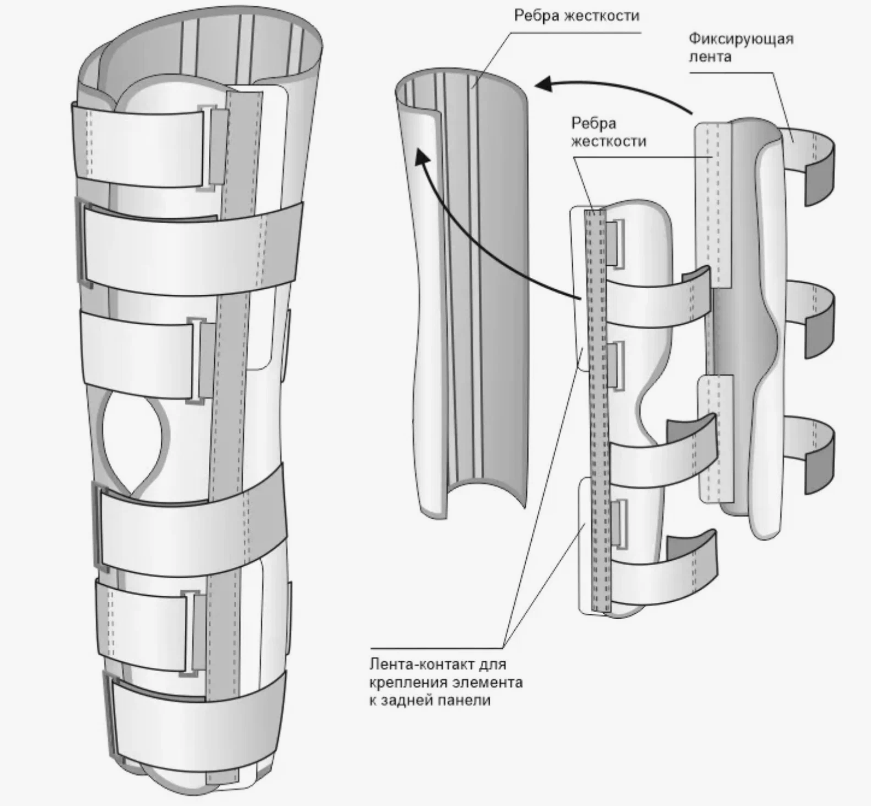

Ортез Orlett на коленный сустав (тутор на коленный сустав) предназначен для иммобилизации (полной фиксации) коленного сустава. Фиксация достигается при помощи 5-ти съемных металлических шин и манжет с ремнями-затяжками, снабженными застежками-липучками «Велкро» (от 4 до 6 в зависимости от размера).

- Предусмотрена возможность индивидуального моделирования металлических шин.

- Длина тутора и количество фиксирующих ремней увеличиваются в зависимости от размера ортеза.

| Конструкция | разъемный, с ребрами жесткости |